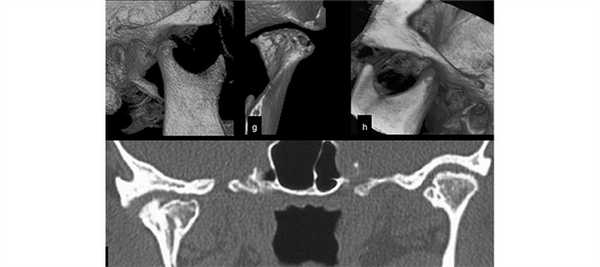

(Слева) На корональной КЛКТ на наружной поверхности шейхи левого мыщелка определяется компактная остеома, образованная плотной костью. Опухоль имеет широкое основание, ровные округлые симметричные контуры.

(Справа) На аксиальной КЛКТ у этого же пациента определяется остеома исходящая из кортикальной пластинки, в остальном имеющей нормальную толщину и плотность. Опухоль симметрична, форма мыщелка в остальном не нарушена.

3. КТ при остеоме височно-нижнечелюстного сустава (ВНЧС):

• КТ в костном окне:

о Однородное, хорошо отграниченное объемное образование кости высокой плотности (рентгеноконтрастное):

- С нормальной трабекулярной картиной

(Слева) На корональной КЛКТ определяется большая остеома в области шейки и головки левого мыщелка, представленная преимущественно плотной кортикальной костью. Кортикальная пластинка шейки мыщелка остается различимой, что помогает отличить остеому от остеохондромы.

(Справа) На аксиальной КЛКТ у этого же пациента визуализируется крупная остеома шейки нижней челюсти с фестончатыми краями, находящаяся скорее на широком основании, чем на ножке.